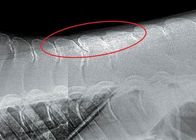

背側棘突起衝突(Kissing Spines) ~ 背骨の突起部分の骨と骨がこすれているためと脊髄部分の骨同士が摩擦を起こして痛みが生じます

背側棘突起衝突は、「キッシングスパイン」としても知られており、馬の背中に激しい痛みをもたらす疾患です。背側棘突起(馬の脊柱から上に突き出た骨の部分)は、棘間靱帯と呼ばれる靭帯で連結されています。正常な馬の背中では、棘突起はお互いに等間隔で並...